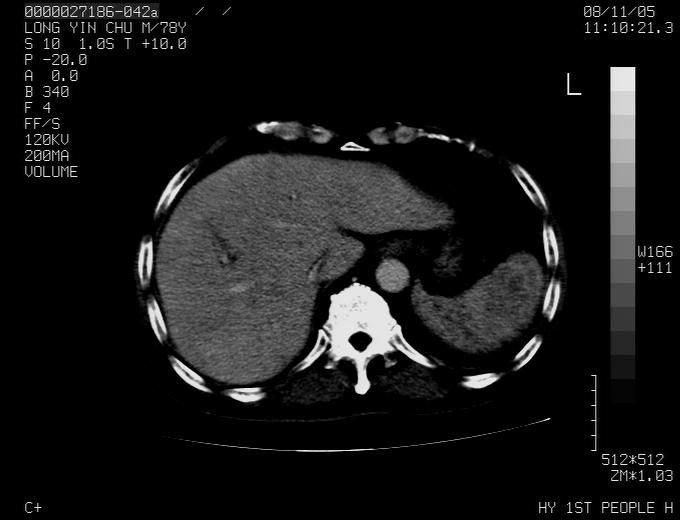

标题: CT16532:M78Y,肝脏病变,请会诊 [打印本页]

标题: CT16532:M78Y,肝脏病变,请会诊

腹胀,腹痛就诊,男性,78岁,外院b超未见异常。

肝ca,脾肾转移

支持脾肾转移瘤,双侧胸腔积液。

考虑弥漫性肝癌并脾及双肾转移.双侧胸水.

图片质量欠佳:多考虑:左侧肾癌。脾脏转移!胸膜转移!

肝脾肾转移瘤可能性大,左肾不除外梗塞,双侧胸水

考虑肝癌并双肾及脾脏转移;双侧胸腔积液。